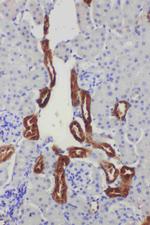

WB IHC (P) ELISA

WB IHC (P) ICC/IF

WB IHC (P)

IHC (P) ELISA